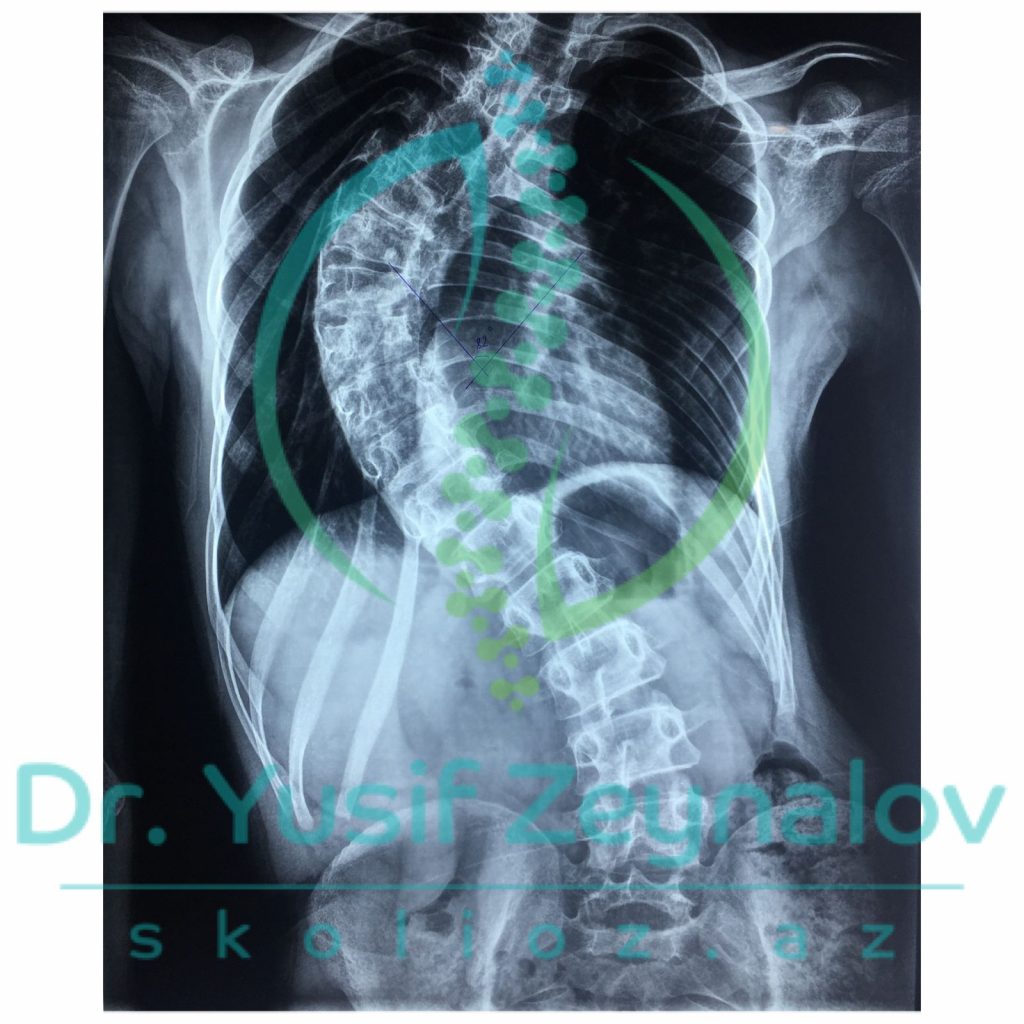

İdiopatik Skoliozlar Səbəbi bəlli olmayan skoliozlardır. Lakin bu skoliotik deformasiyaların yaranma faktorları olduqca çoxdur. İdiopatik skoliozlar zamanı müasir skolioz cərrahiyyəsinin əsasında müasir implantalogiya metodikaları, müasir implantlar, naviqasion sistemlər və 3D modelləşdirmə dayanır. Müasir implantlar və naviqasion sistemlər əvvəllər müalicəsi imkansız hesab edilən ən ağır deformasiyaların belə cərrahi əməliyyatlarını mümkün etmişdir.

-Eyni zamanda müasir skolioz cərrahiyyəsi zamanı 3D modelleşdirmə geniş istifadə edilir. Bele ki, bu metodika vasitasisi ilə oncədən fəqərələrə qoyulacaq implant olçuləri , fəqərə formaları təyin edilir. Öncədən hazırlanmış olçülər hesabına xəstələrədə implantasiya müddəti 2-3 saata enmiş olur. Xəstələrdə əməliyyat zamanı çox hallarda qan transfuziyasına ehtiyac qalmır.